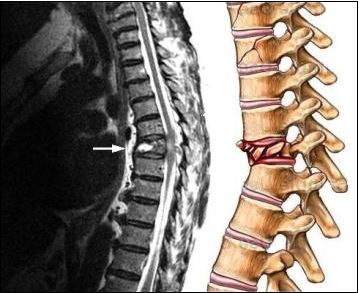

Перелом позвоночника – тяжёлое заболевание, возникающее из-за механических травм, вследствие автомобильных катастроф и падения с большой высоты или даже собственного роста. Пожилые люди часто ломают позвоночник даже при незначительном механическом повреждении тела из-за хрупкости костей, проявляющейся с возрастом. Повреждён может быть, как один позвонок, так и несколько. Травмировать позвоночник можно в любом из отделов: шея, грудь, поясница, крестец.

Симптоматика зависит от тяжести травмы: повреждён спинной мозг или нет. Для диагностирования используется рентген, компьютерная томография, МРТ и другие методы.

- При грубых травмах нередко поражается спинной мозг, что приводит к летальному исходу или инвалидности.

Суть операции - специалист выполняет действия, позволяющие освободить элементы нервной системы от сдавливающих костно-связочных образований от костных фрагментов и выполнить фиксацию, «разгрузку» поврежденного сегмента позвоночника с целью сращения перелома. В ряде случаев, особенно когда речь идет о «взрывном» переломе, применяется этапное лечение, суть которого заключается в замещении неопороспособного тела позвонка или тел на специализированный протез тела позвонка.